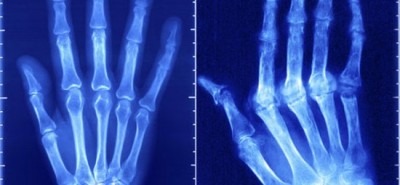

- Припухание суставных флангов указательного и среднего пальцев, лучезапястного сустава с признаками воспалительного процесса.

- Боль в симметрично пораженных суставах обеих рук (чаще в ночью и под утро).

- Деформация суставов стоп рядом с основанием пальцев. Сопровождается болезненными ощущениями при нажатии на пальцы ног.

- Воспалительный процесс в крупных суставах при прогрессировании болезни (плечи, локти, колени). Иногда воспаление начинается именно с крупных суставов, а в последствии переходит на кисти рук.

Наглядная информация про артрит